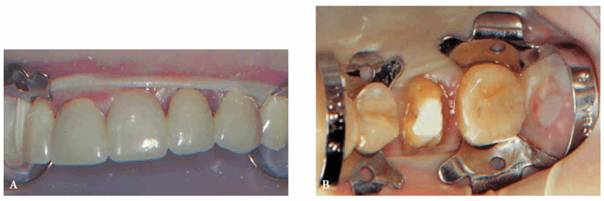

Porcelain Fused-to-Metal Crown. A round diamond stone (Premier 120F

or Gnathos 801-016) accompanied by a copious water spray is best for the

porcelain entry. A classic access cavity is traced in the porcelain (Figure 19-49A). Penetration through the metal and

dentin and into the pulp chamber is accomplished with a new #2 or #1558 carbide

bur (Figure 19-49B). Carbide burs dull rapidly and

should be discarded when they lose their cutting efficiency.

Figure 19-49A: Outline of access cavity traced through porcelain with a diamond stone.

Figure 19-49B: Penetration and funneling of access cavity completed with a carbide bur.